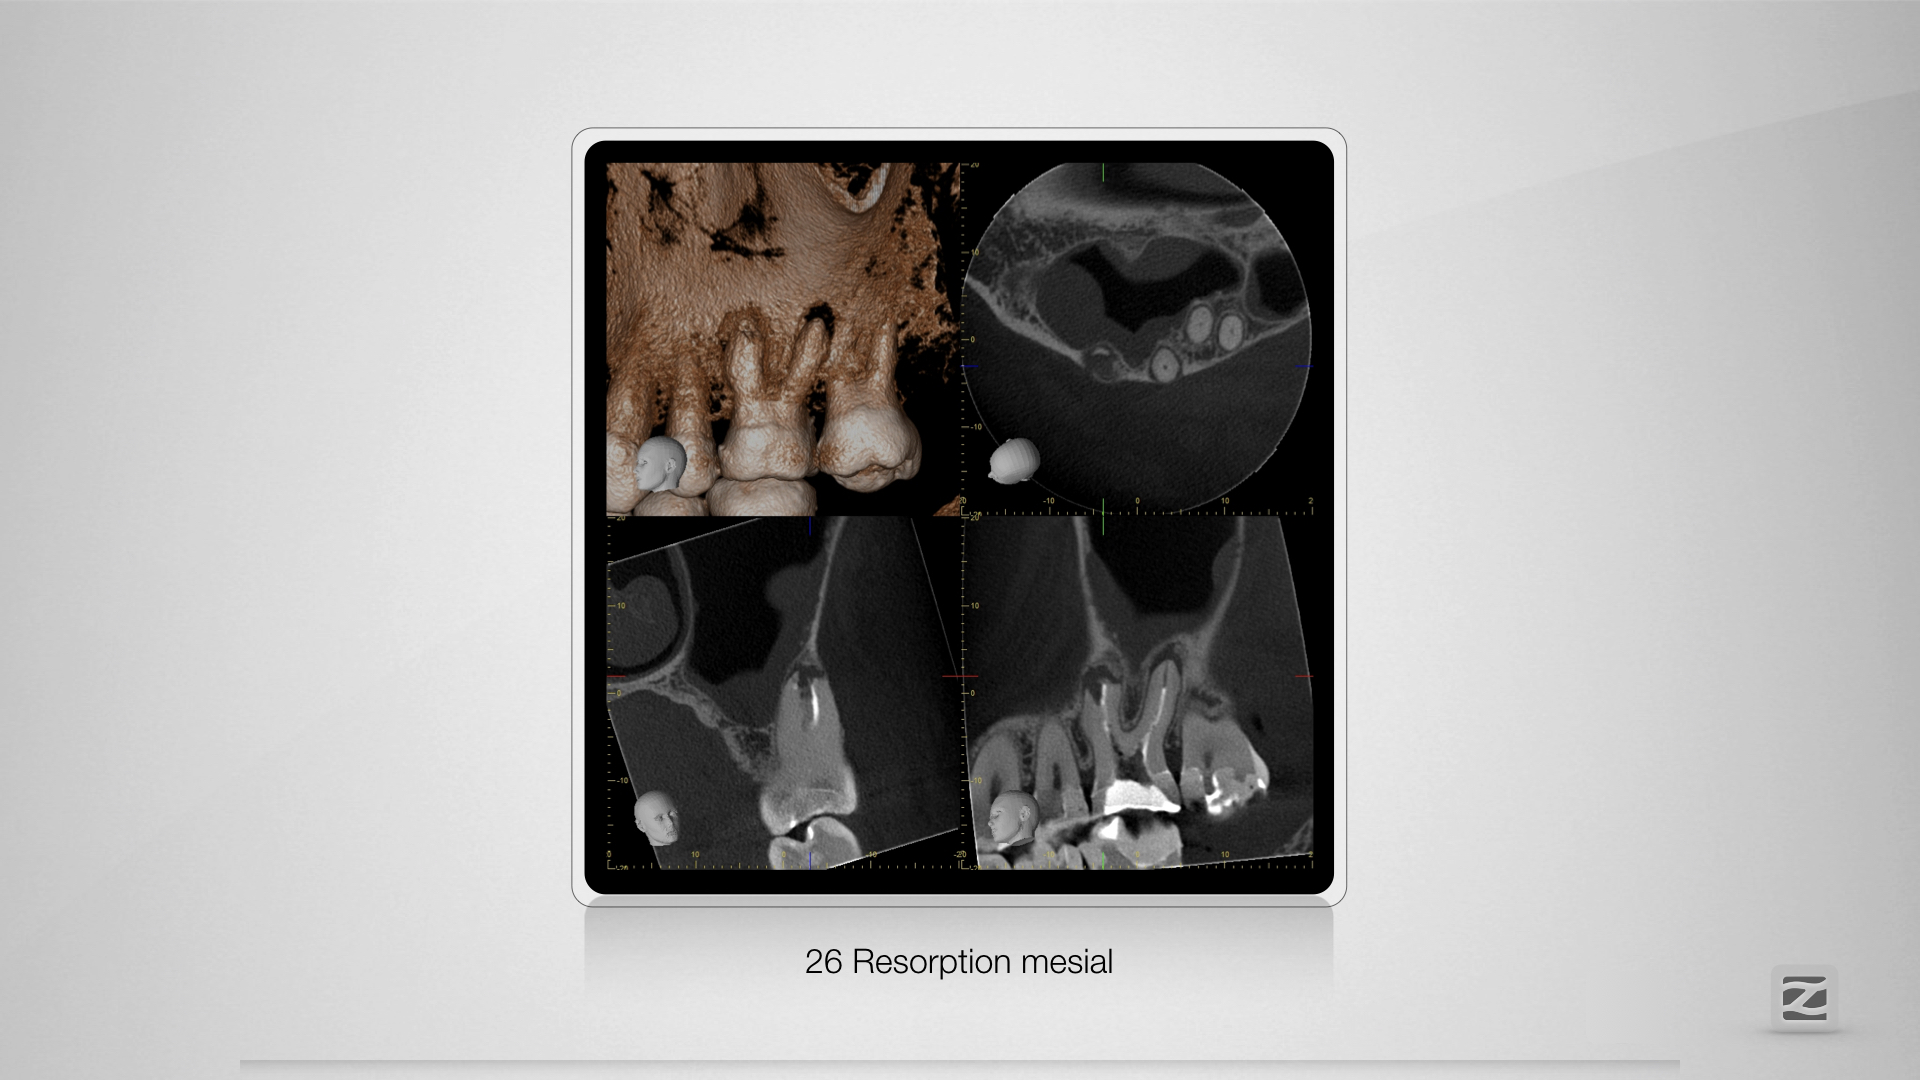

26D.006

Saving hopeless teeth